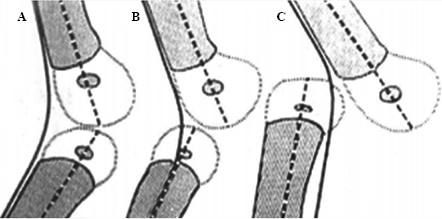

A la hora de establecer un diagnóstico suele ser suficiente con la inspección, puesto que se manifiesta como una marcada hiperextensión de la rodilla, que difiere claramente de la posición fetal normal de la rodilla en el recién nacido.6 La radiología simple es útil tanto para el diagnóstico como para catalogar la lesión mediante la clasificación de Leveuf (Figura 3).2,5 El tipo A es el más frecuente y realmente no es una luxación sino una hiperextensión congénita con una flexión pasiva limitada a 90o. En el tipo B, como nuestro caso, se observa una subluxación congénita con pérdida de la congruencia articular y en el tipo C hay una pérdida completa de la misma.